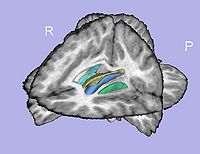

- 1.7. Genus zero cortical surface creation and inflation

- 1.7.2. White matter surface inflation

- Iterative smoothing using relaxation operator (considering average vertex) and L2 norm of the mean curvature as a stopping criterion

- Iteration stopped if vertices that have too high curvature (some extremities)

- Tool: MeshInflation (UNC Slicer3 external module)

- 1.8. Cortical thickness attribute computation

- Cortical thickness interpolation on genus-zero surface

- 1.9. Sulcal depth computation

- Sulcal depth computation using genus-zero surface and inflated one